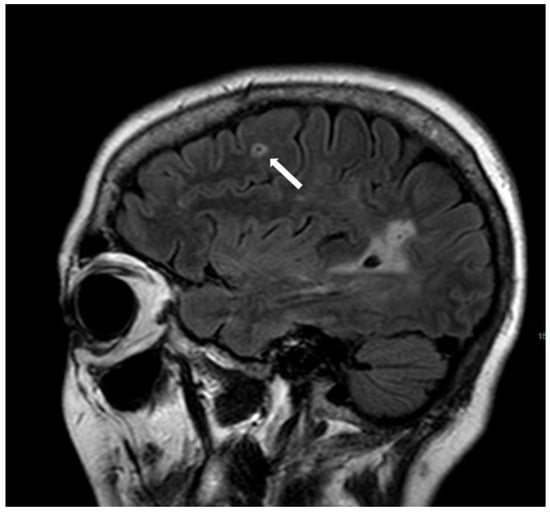

5.1.4. Cortical Superficial Siderosis

6. Neuroradiological Findings That Are Not Part of the Boston Criteria

6.1. Finger-like Projections